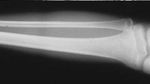

Untuk memperbaiki panjang dan bentuk kaki, dokter menggunakan teknik Ilizarov, dengan alat cincin logam yang perlahan menarik tulang agar tumbuh memanjang. Pemanjangan dilakukan sedikit demi sedikit setiap hari, hingga terbentuk tulang baru di antara celah pemisahan. (Foto: The Journal of Bone & Joint Surgery)

Selama proses ini, lutut dan pergelangan kaki ditopang dengan brace engsel agar tidak terjadi kelainan bentuk. Pasien juga mengikuti fisioterapi intensif agar sendi tetap lentur dan otot tidak melemah. (Foto: The Journal of Bone & Joint Surgery)